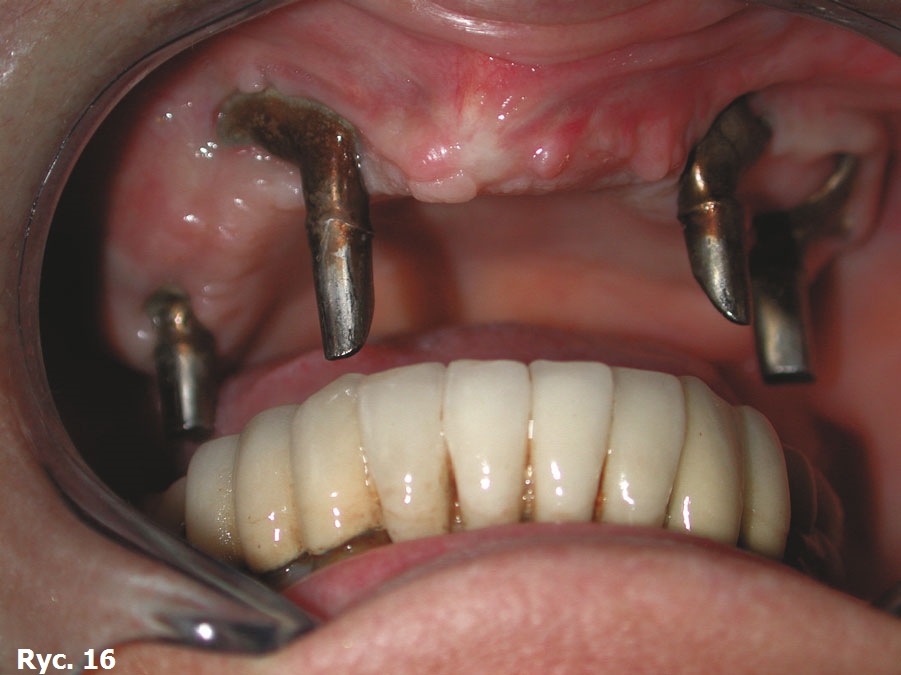

Pacjentka, w wieku 67 lat, całkowicie niezadowolona z użytkowania bardzo niestabilnej górnej protezy całkowitej. Uzyskano informację, że w przeszłości próbowano ją namówić na przeszczep kości, który miał umożliwić wszczepienie implantów, niezbędnych do osadzenia protezy stałej typu full arch. Plan przeszczepienia kości spotkał się z jej zdecydowaną odmową. W jednym z gabinetów szczegółowo wyjaśniono pacjentce również, na czym polega zabieg wszczepienia siatek podokostnowych oraz osadzenia stałego uzupełnienia protetycznego typu full arch. Pacjentka natychmiast poprosiła o zaopatrzenie bezzębia za pomocą podokostnowych wszczepów siatkowych.

Obrazy TK oraz modele stereolitograficzne ukazują wysoki stopień zaniku tkanek twardych szczęki. Z tego powodu wykonano projekt wszczepu podokostnowego full arch (ryc. 14), który odlano z 5. gatunku tytanu (ryc. 15) i wszczepiono. Zabieg odbył się bez powikłań (ryc. 16). Leczenie zakończyło się wykonaniem i oddaniem protezy stałej full arch typu all on four, która w pełni zaspokaja estetyczne oraz funcjonalne oczekiwania pacjentki (ryc. 17, 18, 19, 20, 21).

Wszczepy podokostnowe - przypadek 3 (ryciny)